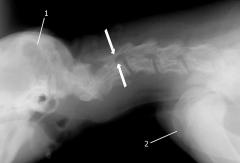

Als bildgebendes Verfahren findet routinemäßig die Röntgendarstellung Anwendung. Allerdings stellen sich im Röntgenbild Stenosen nicht immer deutlich dar, vor allem wenn eine seitliche Verengung vorliegt. Eine Myelografie kann die Diagnose sichern, allerdings reicht die Hülle der harten Hirnhaut (Dura mater) in 20 % der Fälle nur bis zum letzten Lendenwirbel.

Dagegen ist das Anfertigen einer einfachen Röntgenaufnahme nicht immer hilfreich, da sich die vorgefallenen Bandscheibenanteile meist im Röntgen nicht deutlich nachweisen lassen.

Mittels einer Myelographie ist die Eingrenzung des Schadens jedoch in der Regel möglich. Letzte Sicherheit über das Ausmaß des Schadens kann eine Magnetresonanztomographie geben.